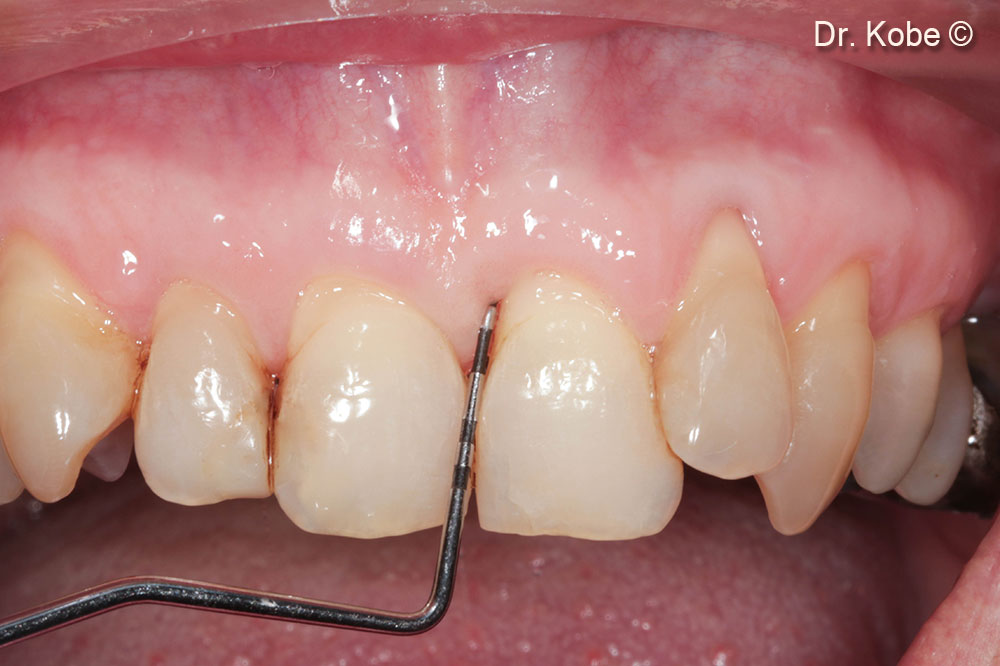

Treatment of a periodontal defect with the Entire Papillae Preservation Technique (EPPT)

Dr. Tom Kobe

Initial situation

A female patient (47 years old) shows a periodontal defect

1. Initial situation